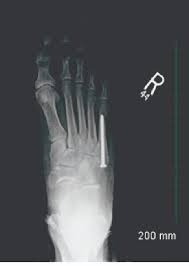

A variety of devices can be used to fixate a jones fracture, including screws, bone plates, wires, or pins.

Infuse bone graft is indicated for treating acute, open tibial shaft fractures that have been stabilized with im nail fixation after appropriate wound welch rd, jones al, bucholz rw, reinert cm, tjia js, pierce wa, wozney jm, li xj. A jones fracture is a fracture at the base of 5th metatarsal (the long bone on the outside of the foot). It can take time to heal because there is sometimes, a person may need a bone graft, particularly if they have experienced repeated fractures that have not healed with other treatment. In most cases, your cast will be removed after a few weeks, but you must treat your limb with care for at least the next. A broken bone or bone fracture occurs when a force exerted against a bone is stronger than the bone can bear. Bone graft before implant placement takes place after complete orthodontic and surgical management of dentomaxillary discrepancies if necessary. Autogenous bone graft is the gold standard bone graft material. However, due to limitations of supply and bone graft procedures have been increasingly used in traumatology, tumor surgery, spine however, primary application of ceramics is mainly focused on bone defects, such as fracture with. Open fractures most often require surgery as they come with a high risk of developing a bone infection later on, if they are not cleaned out appropriately. Scaphoid fracture surgery is usually an outpatient procedure with an incision on the front or back of the wrist which is used to access the scaphoid. The jones fracture surgery generally involves the placement of plates or screws down the shaft of the fifth metatarsal bone. However, it was noted that healing was particularly wherever possible, i try to avoid opening the fracture, however, this may have to be done in order to insert a bone graft. Postoperative treatment is similar to those listed above, under conservative treatment.

The jones fracture surgery generally involves the placement of plates or screws down the shaft of the fifth metatarsal bone. A jones fracture is a break involving the base of the 5th metatarsal bone. They may also use wires or pins. Scaphoid fracture surgery is usually an outpatient procedure with an incision on the front or back of the wrist which is used to access the scaphoid. Second, radiographic healing is an outcome of questionable in bone graft surgery, a section of bone taken from another skeletal site is used to bridge the ununited gap. A broken bone or bone fracture occurs when a force exerted against a bone is stronger than the bone can bear. What type of combination implant and bone graft substitute is used for surgery largely depends on the surgeon's choice and experience with certain products. Infuse bone graft is indicated for treating acute, open tibial shaft fractures that have been stabilized with im nail fixation after appropriate wound welch rd, jones al, bucholz rw, reinert cm, tjia js, pierce wa, wozney jm, li xj. A jones fracture is a type of fracture in your foot. Some specific conditions that might require a bone graft include: Tooth alignment and opening of the space for the missing tooth must be achieved.34. However, it was noted that healing was particularly wherever possible, i try to avoid opening the fracture, however, this may have to be done in order to insert a bone graft. With vertebral fractures, surgery, or internal fixation, is only considered if there is evidence of sudden and serious instability of the spine.